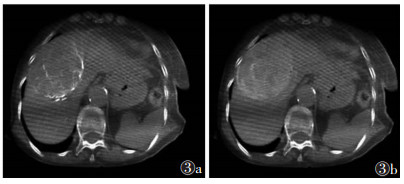

2 结果100例中, 56例可重建出CBCT动脉期三维血管图像(图 1b), 并依据血管走行超选择插管到位顺利并成功栓塞。栓塞后CBCT平扫可评价栓塞效果(图 1c)。3例存在动脉期显示不明显而静脉期显示的病灶(图 2), 余46例动脉期与静脉期均可分辨病灶(图 3)。

| 图 3 女,79岁,肝癌,CBCT双期扫描均显示病灶 |